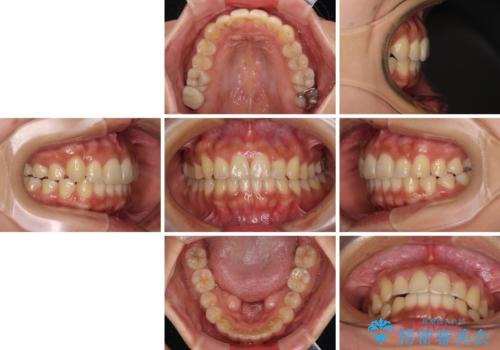

【モニター】歯列が狭くデコボコが気になる 急速拡大装置を用いたインビザライン矯正

- 患者様

- 30代女性

上下の骨幅を改善したことで、スムーズに歯列矯正を行うことができました。

土台のまま放置されていた歯は土台の状態で咬み合っていましたが、急速拡大を行った際に咬み合わせが著しく挙上されたため、その際に土台を大きくすることで咬み合う歯との距離を確保しました。